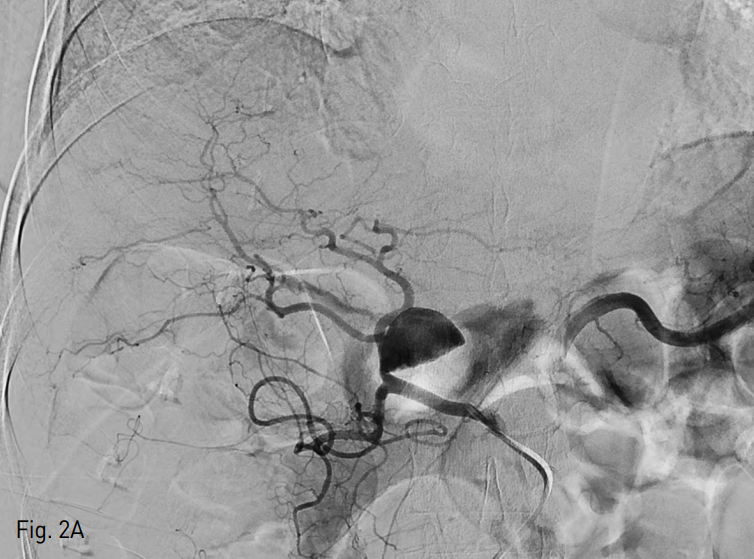

Fig. 2. Balloon-assisted coil embolization

A. DSA images showed partially thrombosed aneurysm (arrow) at the proper hepatic artery.